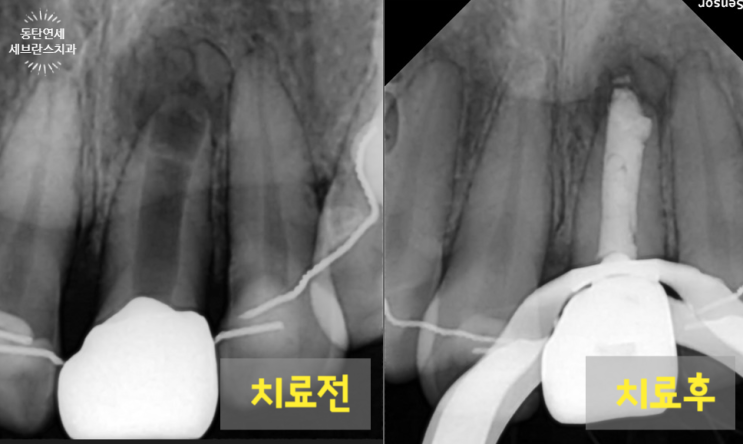

신경이 어마무지하게 큰 앞니의 신경치료, 치근단 수술 없이 완료했어요.

안녕하세요. 오늘은 제가 지금까지 치료한 치아 중 가장 신경이 넓었던 치아의 신경치료 케이스에 대해 보...